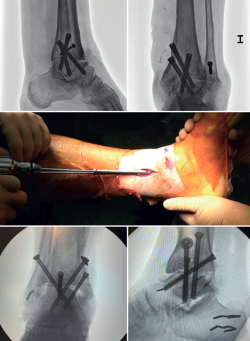

Another option preferred by some authors is, having removed the leg supports from the operating table, to clamp the thigh of the limb with a leg brace so that the hip is flexed about60°, with the knee flexed and mobile, allowing the ankle to fall free(16,17) (Figure 3).

Figure 3. Different limb positioning for arthroscopic ankle arthrodesis procedures. Depending on the surgeon's preference, a thigh brace may be used and, with the knee in flexion, the ankle may be left to hang down under gravity. Another option is to work in the semi-flexed knee position on the operating table. Finally, the traditional supine position on the operating table, with the knee in extension.